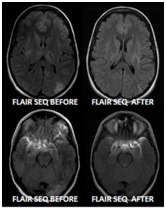

A 56-year-old female presented, with headache and high blood pressure >218/119mm of Hg. Newly discovered renal impairment was seen with Urea of 24.87mmol/l, and Creatinine of 668.4mmol/l. Her GCS dropped showed prompted diffuse signal alteration and edema of brain stem. There is bilateral signal alteration seen in the pons and midbrain seen bilaterally, which shows improvement, with bilateral cerebellar peduncle as well as dentate nucleus, not seen in imaging. Diffuse signal alteration and edema of brain stem. DWI images displayed no evidence restriction or acute infarction. Findings are suggestive of hypertensive encephalopathy (Central-Variant PRES). Follow up images after treatment revealed significant improvement. In short MRI Brain which showed central variant of PRES, which shows resolution on repeat scan, see case and Figure 3.

Figure 3 Diffuse signal alteration and edema of brain stem. There is signal alteration of bilateral cerebellar peduncle as well as dentate nucleus (not seen in this image). DWI images displayed no evidence restriction or acute infarction. Findings are suggestive of hypertensive encephalopathy (Central-Variant PRES). Follow up images after treatment revealed significant improvement.